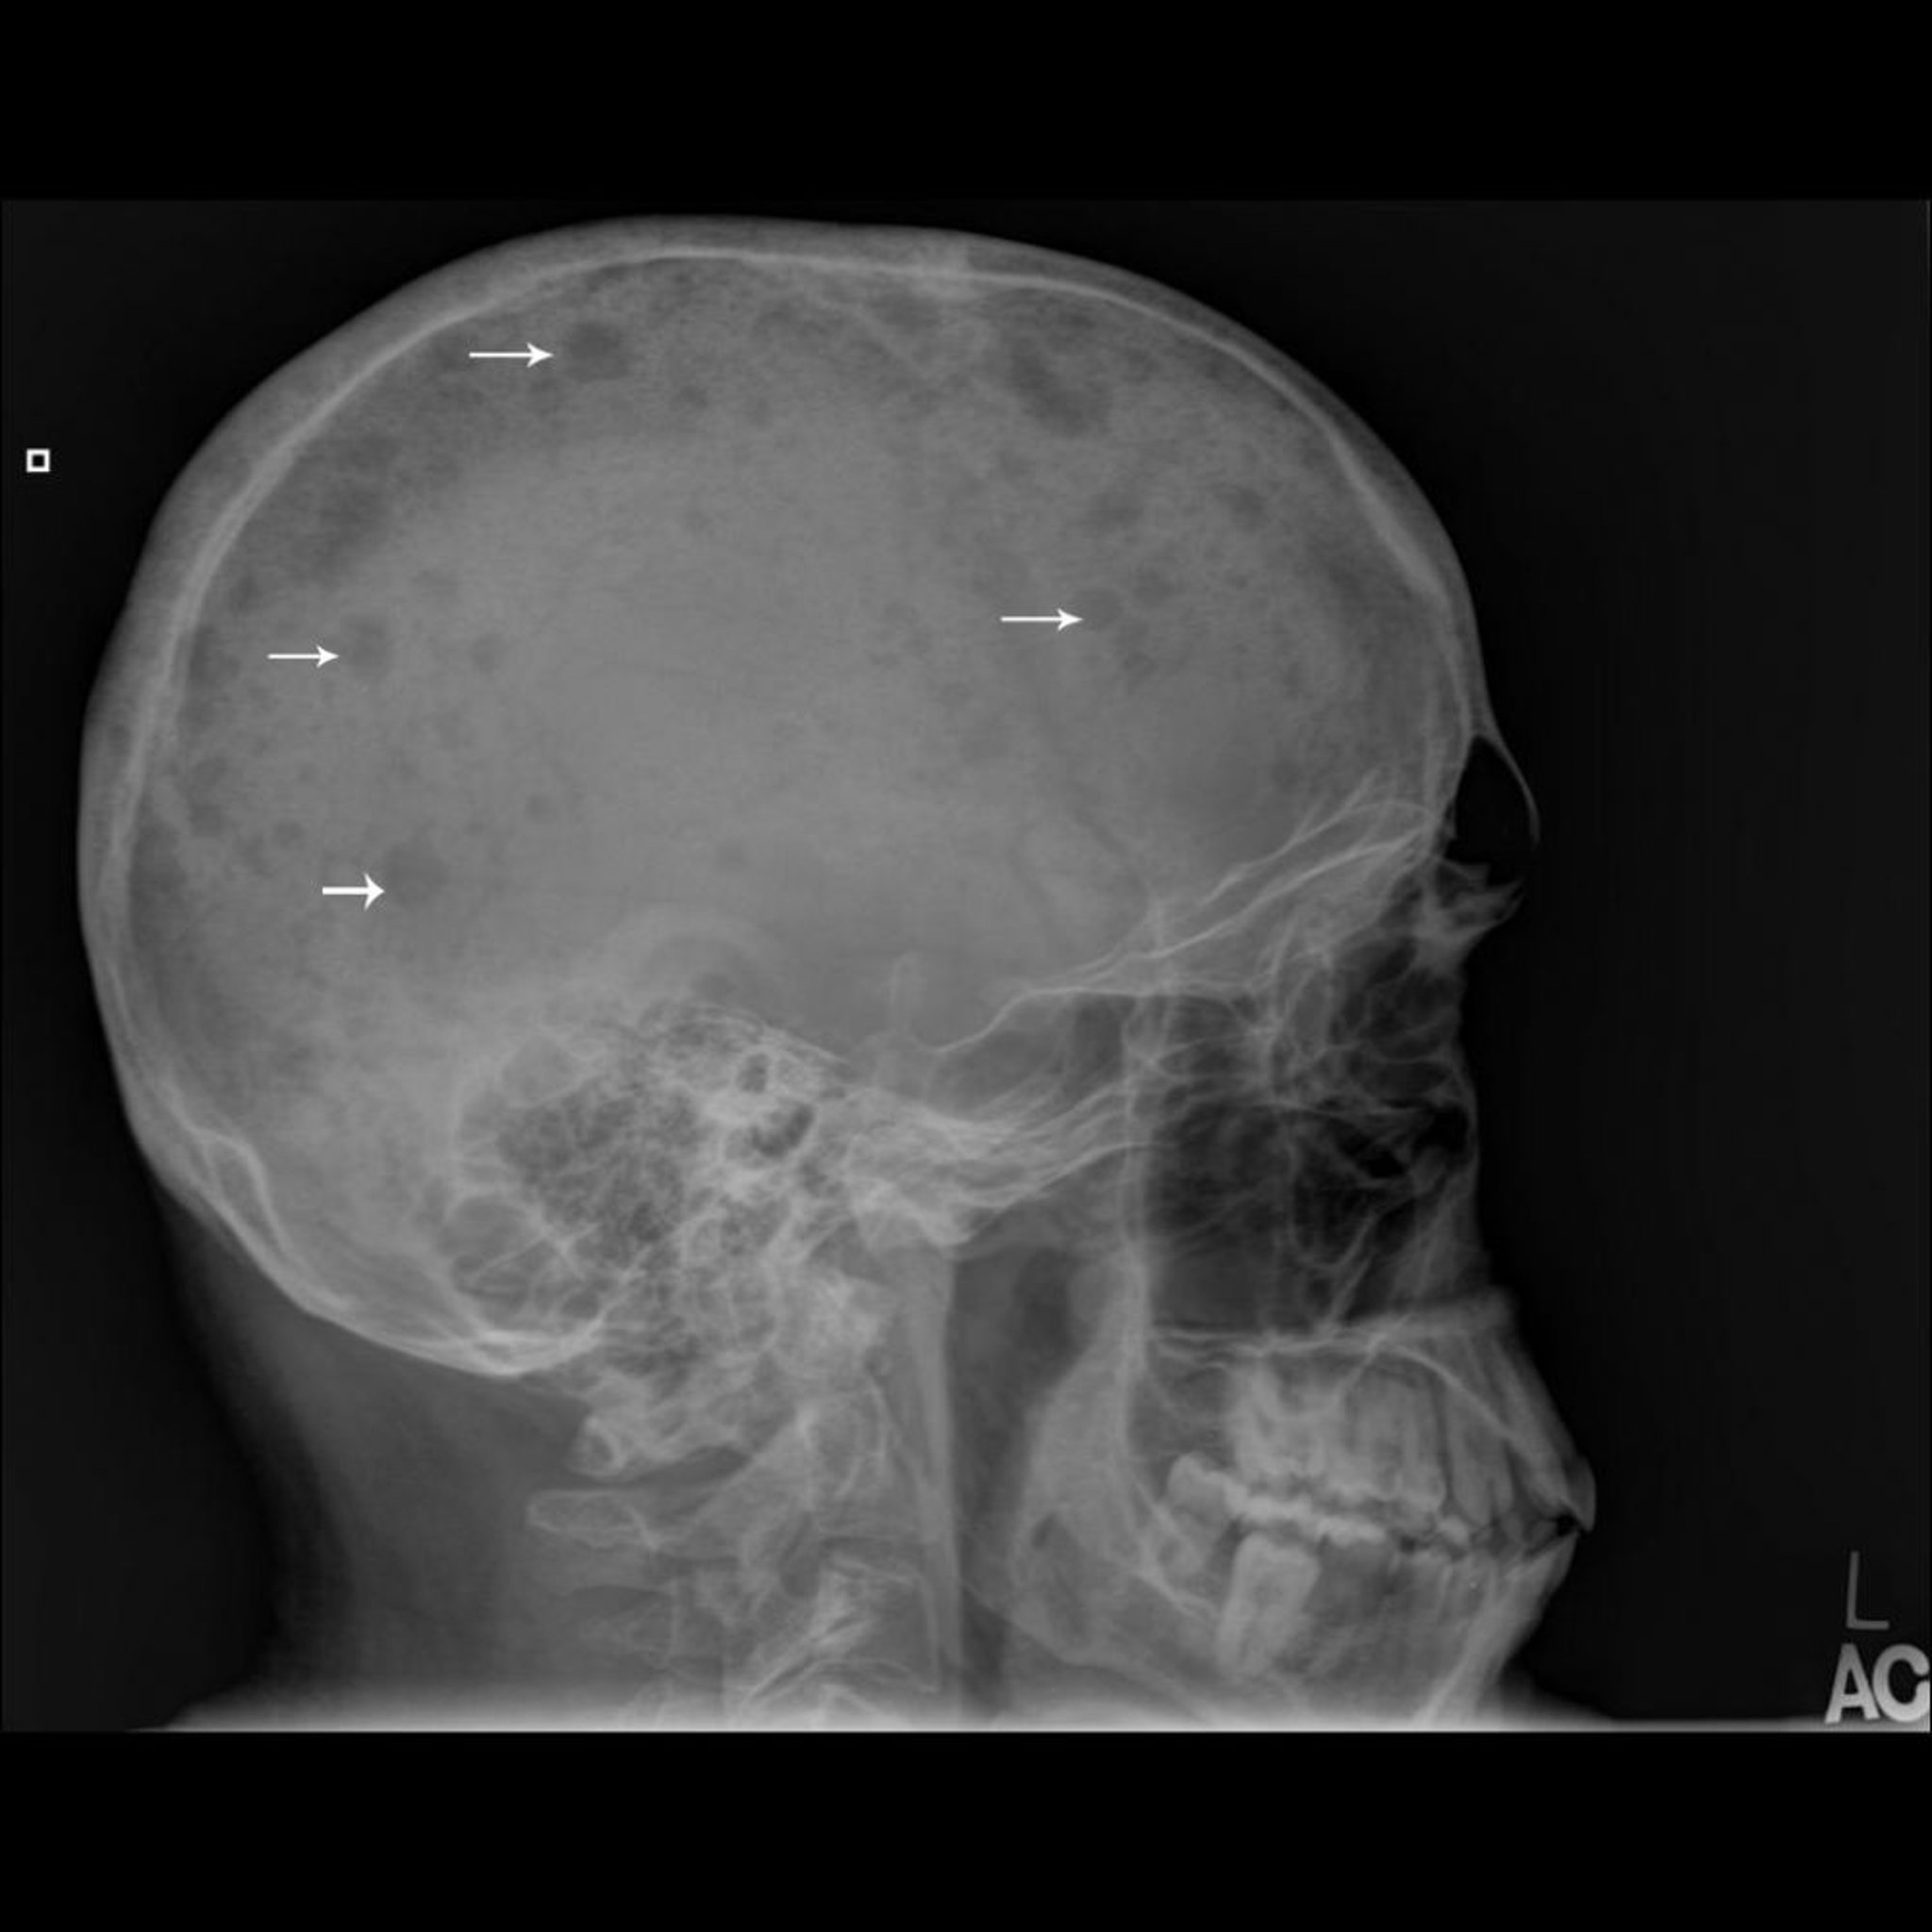

Множественная миелома

На этой рентгенограмме показано множество участков кости, по виду напоминающих пробитые пробойником отверстия (стрелки), что характерно для множественной миеломы.

Изображение любезно предоставлено д-ром Майклом Дж. Джойсом (Michael J. Joyce) и д-ром Хаканом Иласланом (Hakan Ilaslan).